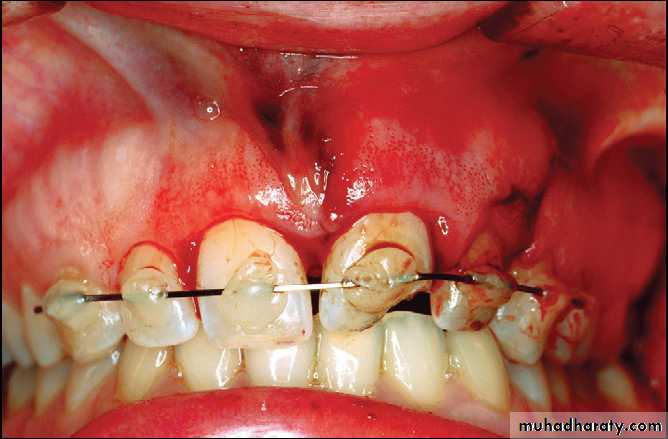

Platally displaced central and lateral incisors in apically mature tooth.

Position of teeth after digital reduction and stabilization with bonded arch wire.- Intrusion